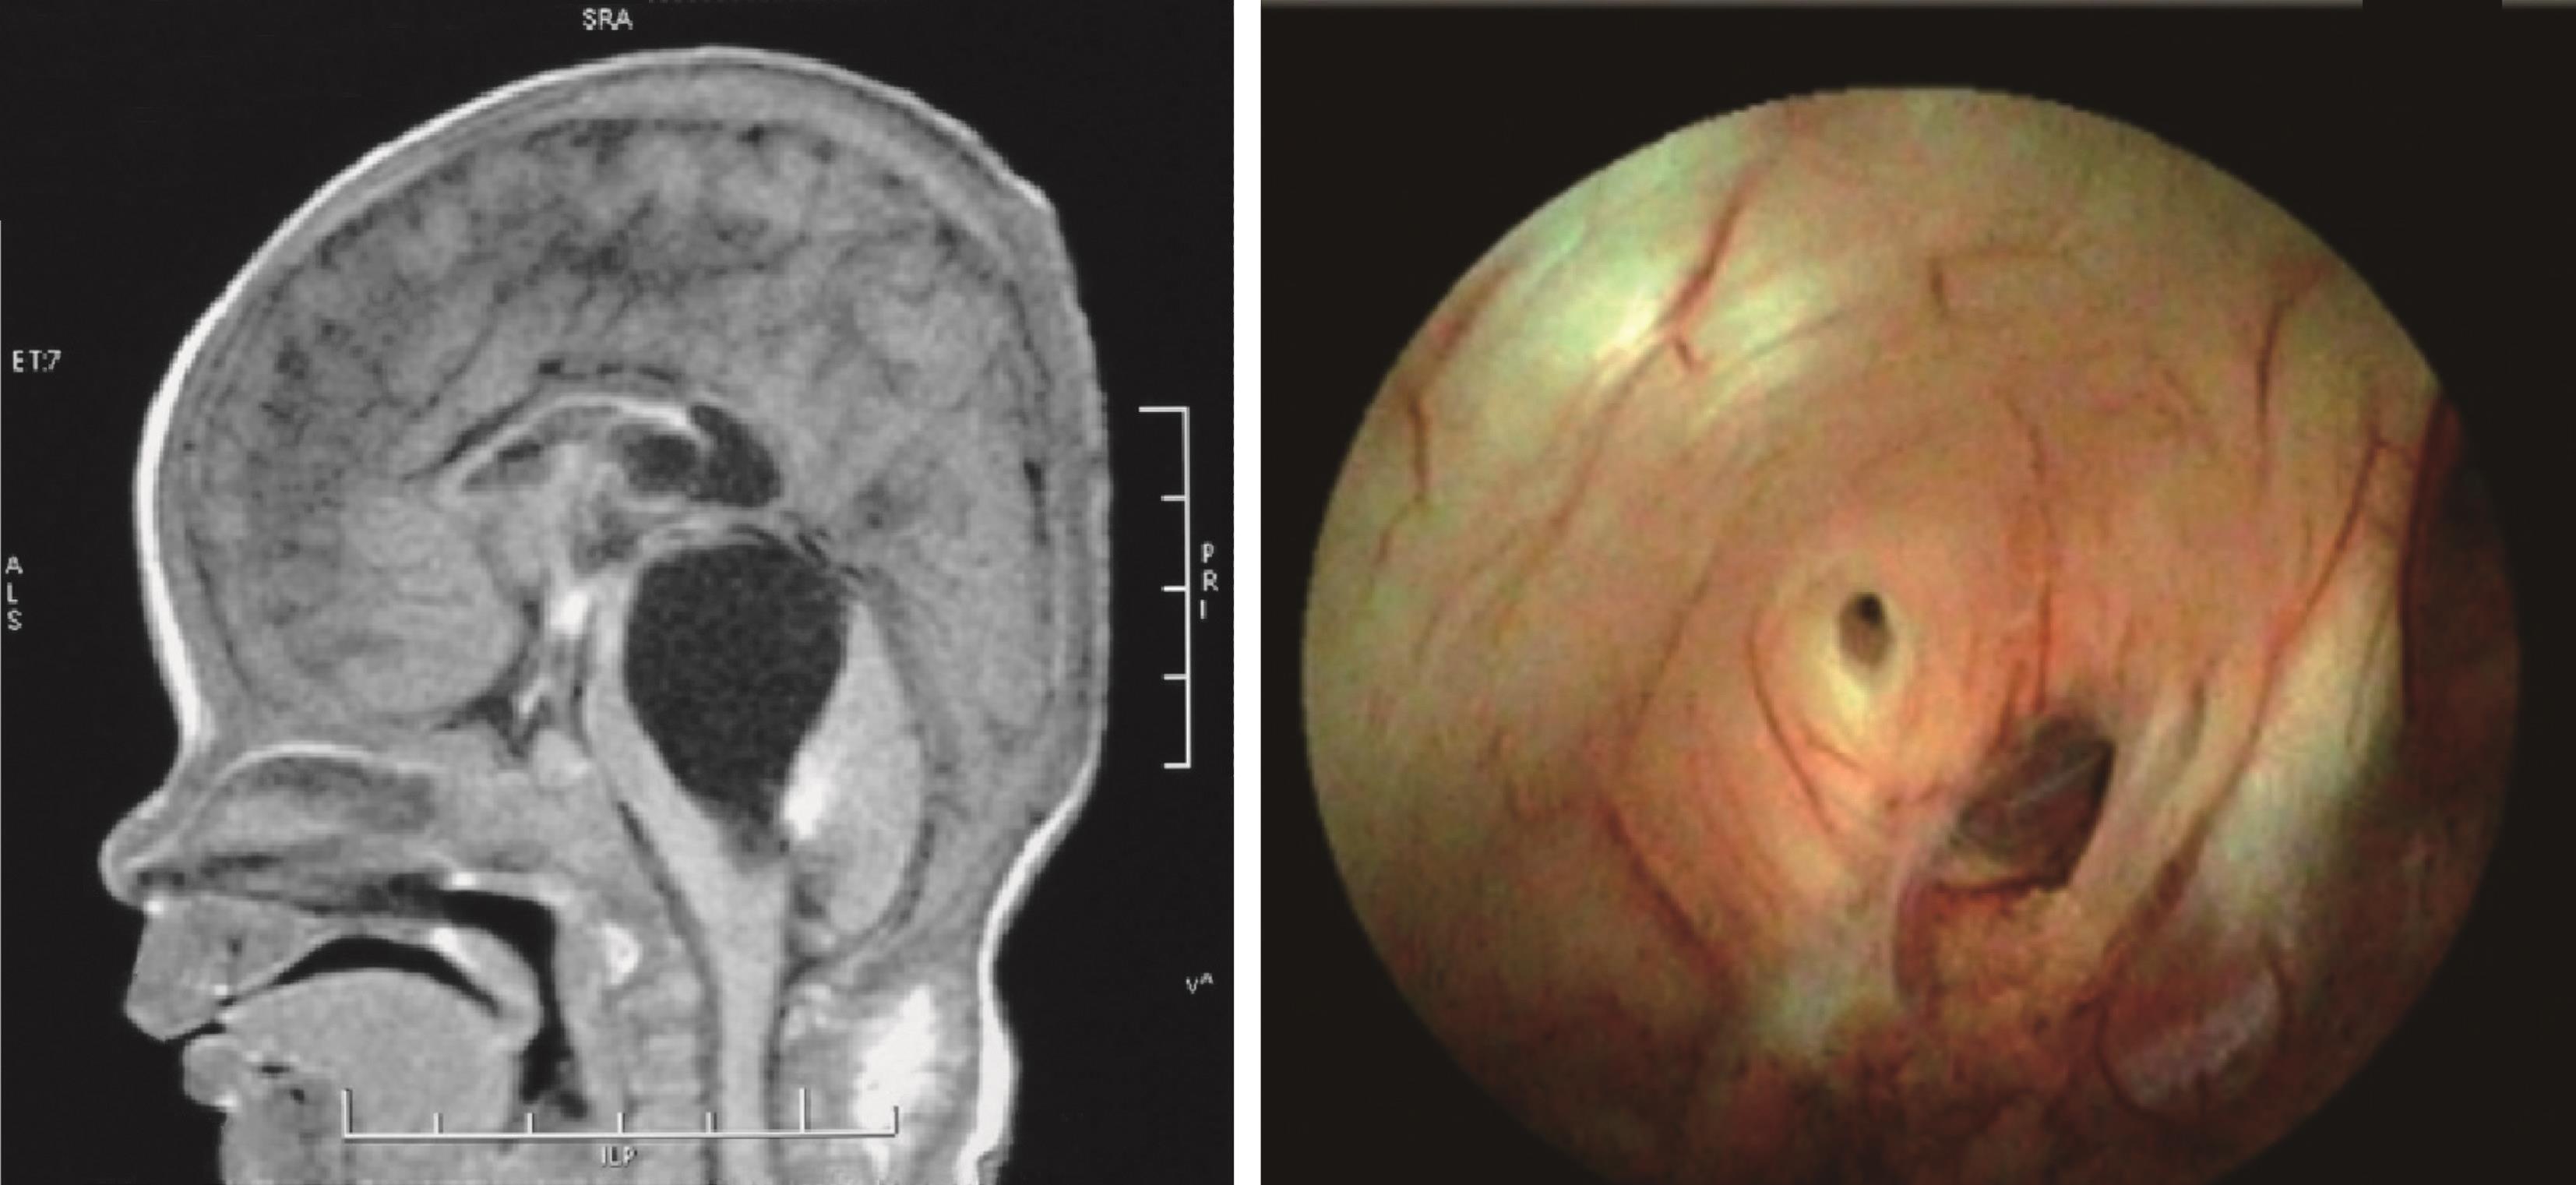

10.有些合并Chiari畸形的脑积水,单纯行内镜下第三脑室底造瘘术,改变颅腔和脊髓蛛网膜下腔之间的压力梯度后,下疝的小脑扁桃体可以还纳,临床症状缓解(图 3-1-2-11)。

图3-1-2-11 脑积水合并Chiari畸形

a.术前MRI矢状位片示脑积水,小脑扁桃体下疝;b.第三脑室底造瘘术后1周,MRI矢状位片示小脑扁桃体下疝减轻